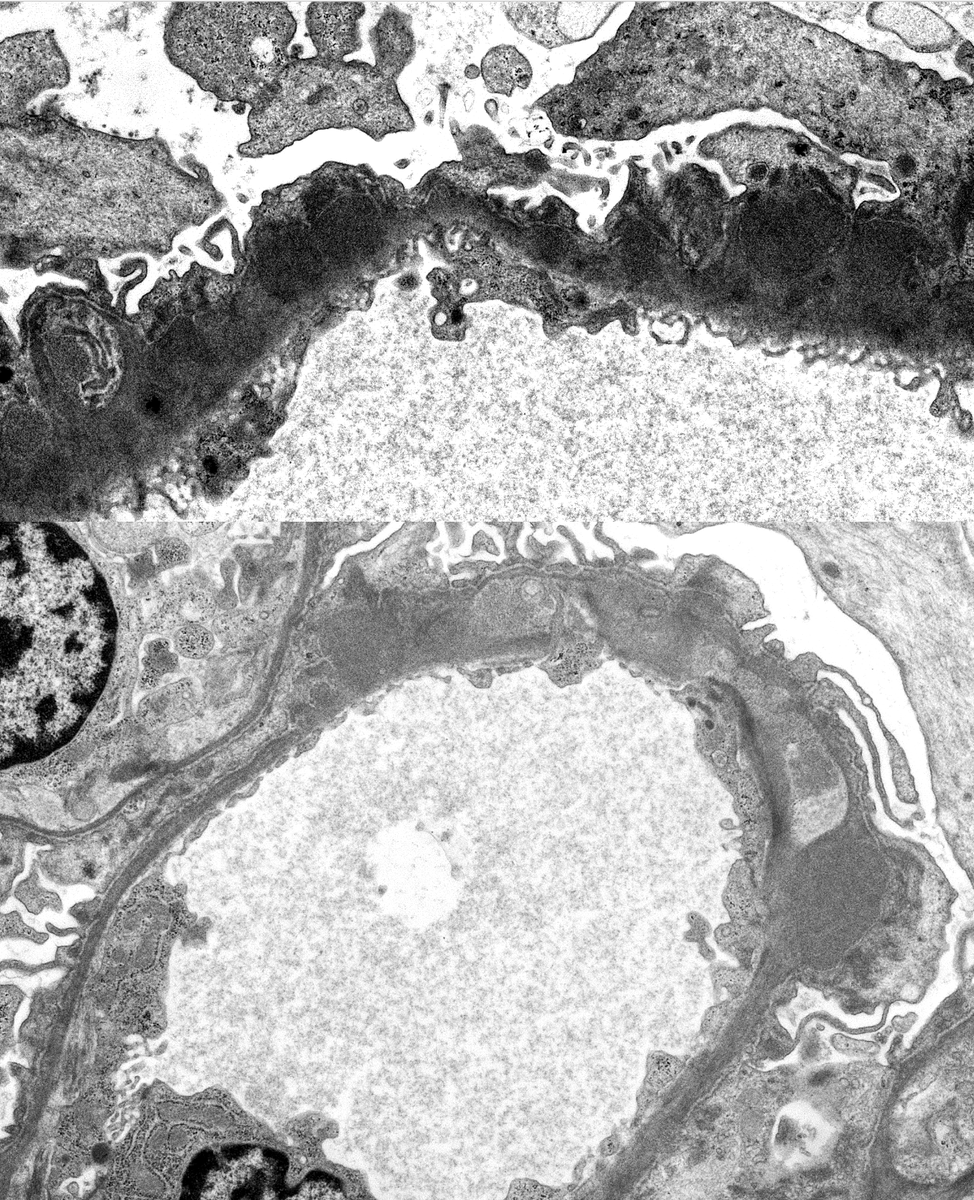

The picture shows tissue submitted for routine immunofluorescence (fibrinogen stain is shown). Careful inspection confirms that this is an artery cross section which contains abnormal intraluminal tissue elements with numerous cleft-like spaces (see arrow). Although no immune